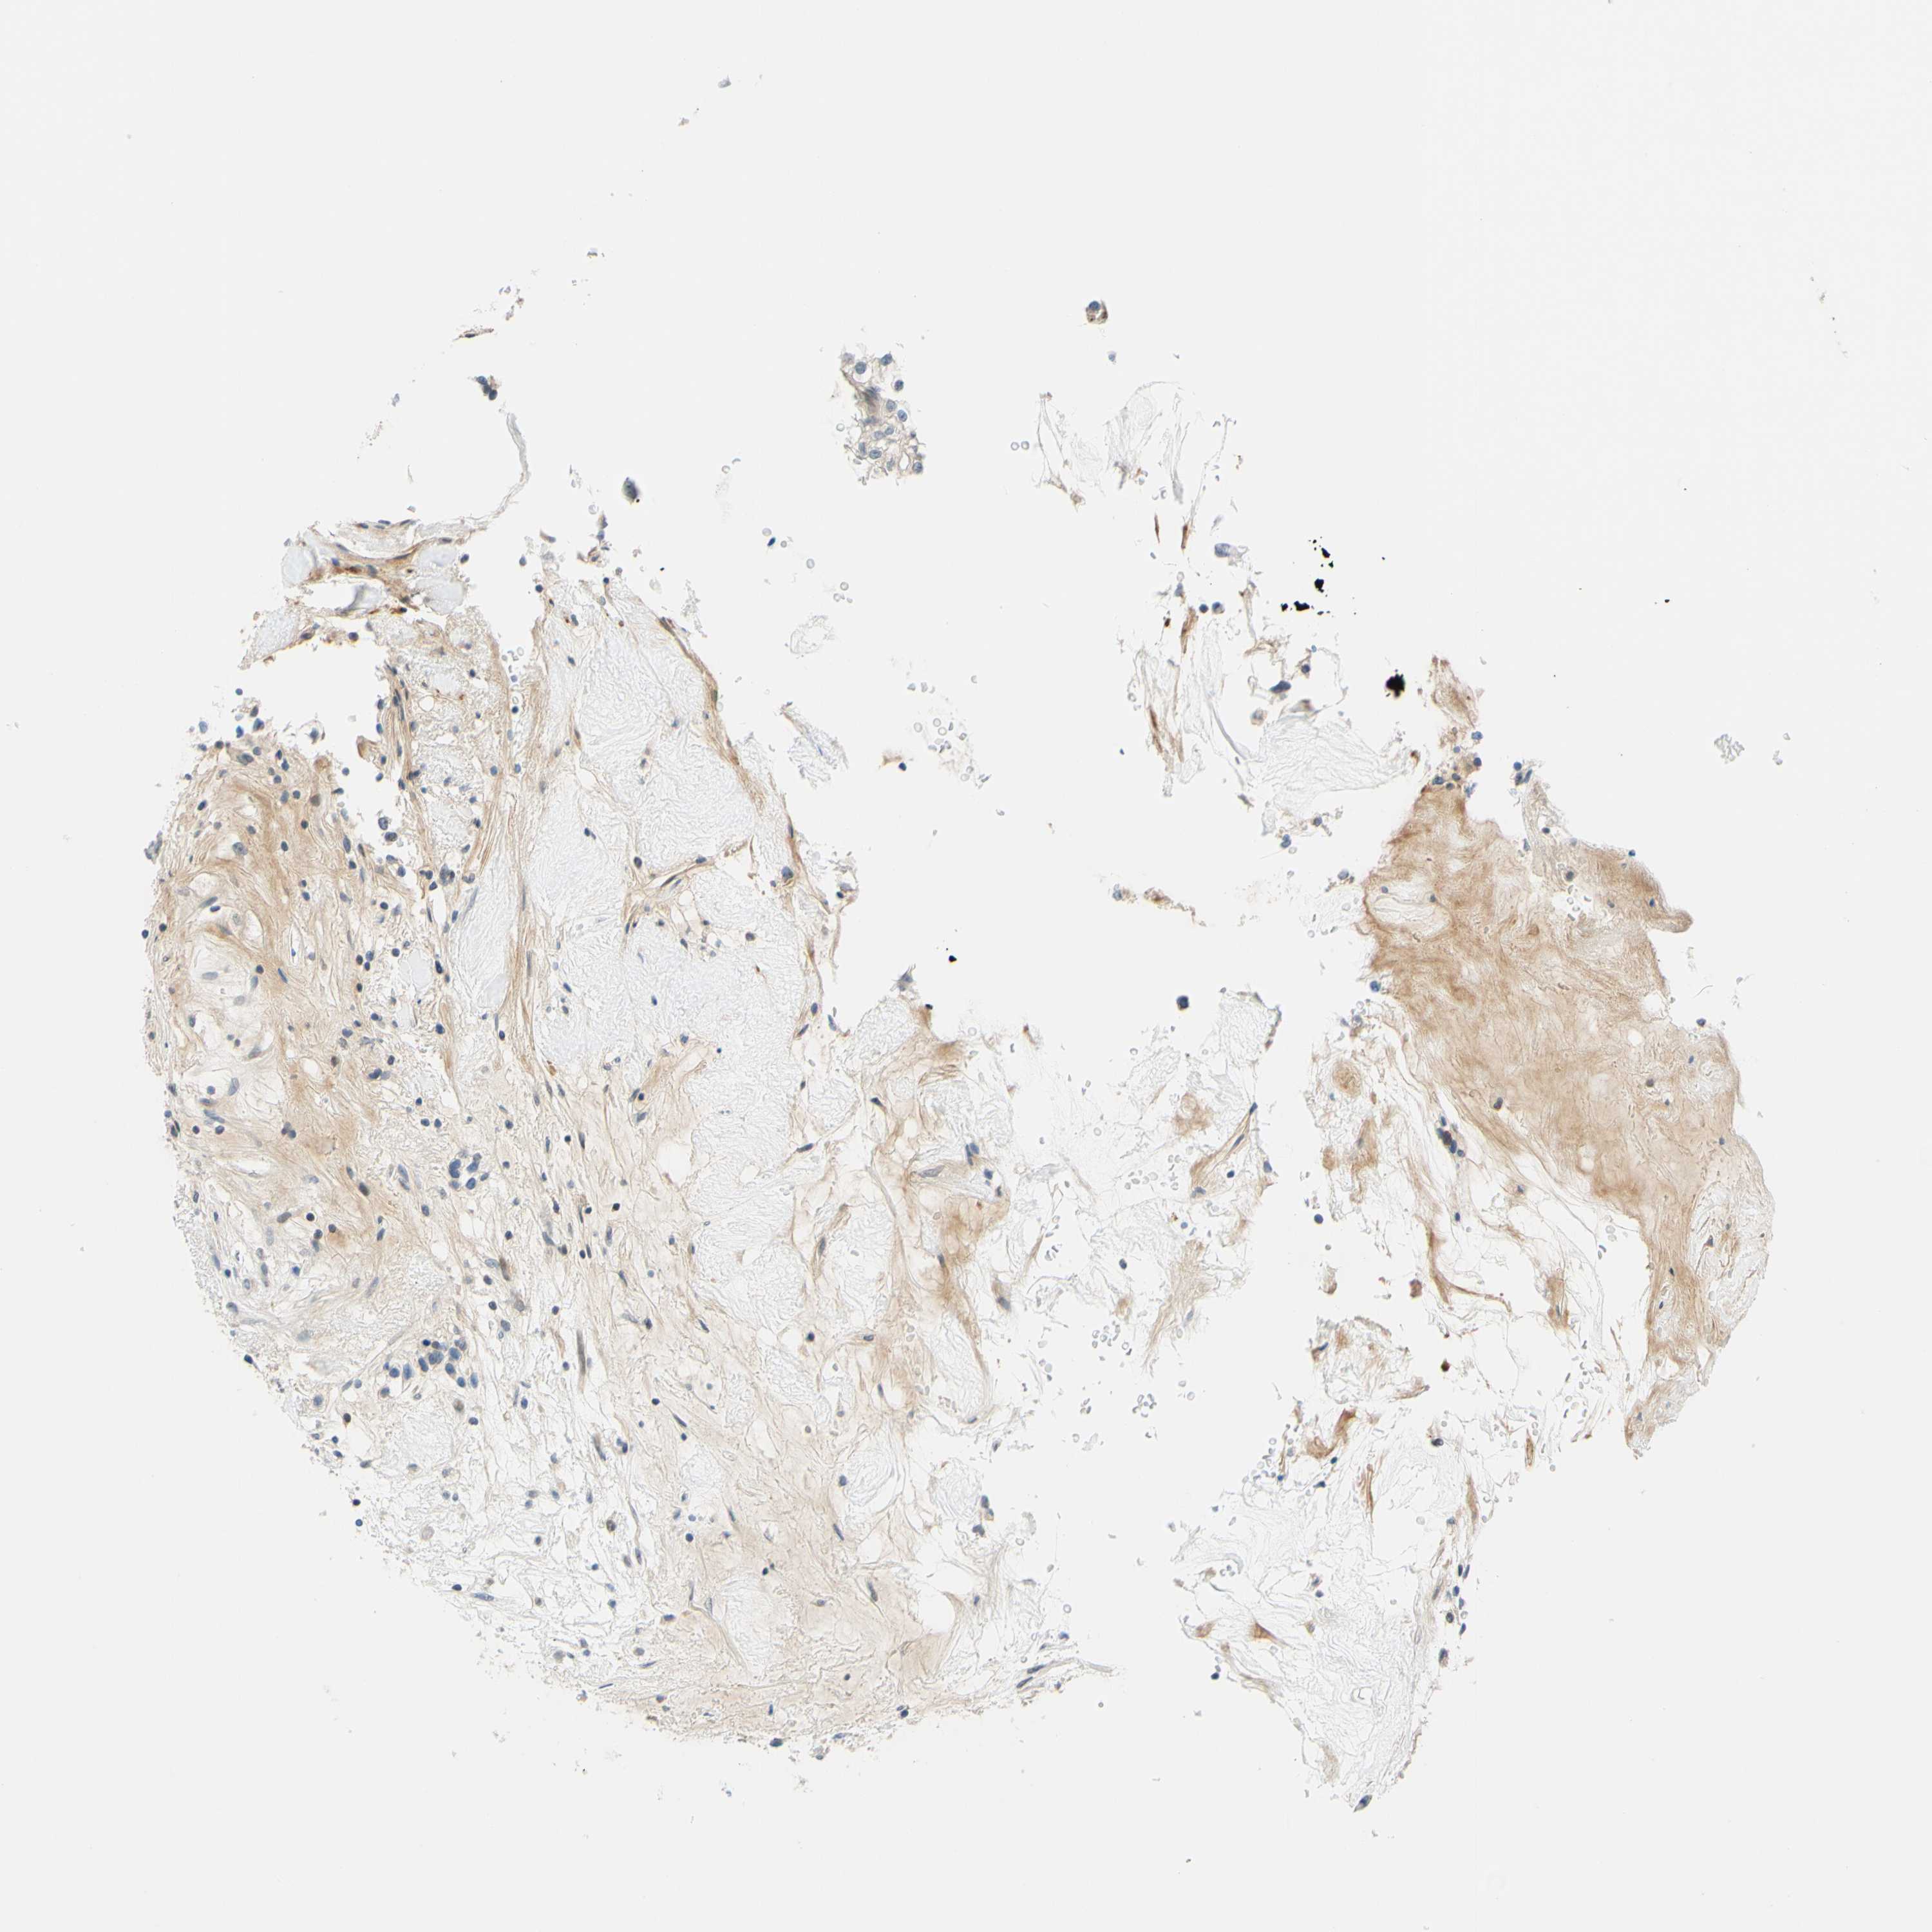

KIDNEY RENAL CLEAR CELL CARCINOMA (TCGA) - Interactive survival scatter ploti

The Survival Scatter plot shows the clinical status (i.e. dead or alive) for all individuals in the patient cohort, based on the same data that underlies the corresponding Kaplan-Meier plots. Patients that are alive at last time for follow-up are shown in blue and patients who have died during the study are shown in red.

The x-axis shows the expression levels (FPKM) of the investigated gene in the tumor tissue at the time of diagnosis. The y-axis shows the follow-up time after diagnosis (years). Both axes are complimented with kernel density curves demonstrating the data density over the axes. The top density plot shows the expression levels (FPKM) distribution among dead (red) and alive patients (blue). The right density plot shows the data density of the survived years of dead patients with high and low expression levels respectively, stratified using the cutoff indicated by the vertical dashed line through the Survival Scatter plot. This cutoff is automatically defined based on the FPKM cutoff that minimizes the p-score. The cutoff can be changed by dragging the vertical line or by entering a cutoff value in the square labeled "Current cut-off".

Under the Survival Scatter plot the p-score landscape (black curve; left axis) is shown together with dead median separation (red curve; right axis). Dead median separation is the difference in median mRNA expression between patients who have died with high and low expression, respectively. It is calculated as follows: median FPKM expression of dead patients with high expression - median FPKM expression of dead patients with low expression. This is intended to aid the user in visually exploring custom cutoffs and the associated p-scores and dead median separation.

Individual patient data is displayed and can be filtered by clicking on one or more of the category buttons on the top of the page. Categories describing expression level and patient information include: high, low, alive, dead, female, male and tumor stages. The scale of the x-axis can be toggled between linear and log-scale by clicking on the "x log" button. Mouse-over function shows TCGA ID, patient information and mRNA expression (FPKM) for each patient.

& Survival analysisi

Kaplan-Meier plots summarize results from analysis of correlation between mRNA expression level and patient survival. Patients were divided based on level of expression into one of the two groups "low" (under cut off) or "high" (over cut off). X-axis shows time for survival (years) and y-axis shows the probability of survival, where 1.0 corresponds to 100 percent.

C2CD2L is not prognostic in Kidney Renal Clear Cell Carcinoma (TCGA)

Best expression cut offi

Based on the FPKM value of each gene, patients were classified into two groups and association between prognosis (survival) and gene expression (FPKM) was examined. The best expression cut-off refers the FPKM value that yields maximal difference with regard to survival between the two groups at the lowest log-rank P-value. Best expression cut-off was selected based on survival analysis .

When clicking on this number, the vertical dashed line indicating cut-off, the interactive survival plot, and the Kaplan-Meier curve will be adjusted to show results based on the best expression cut-off.

: 6.76

Median expressioni

Median expression refers to the median FPKM value calculated based on the gene expression (FPKM) data from all patients in this dataset. When clicking on this number, the vertical dashed line indicating cut-off, the interactive survival plot, and the Kaplan-Meier curve will be adjusted to show results based on the median expression.

: N/A

Median follow up timei

Median follow up time refers to the median time (years) after diagnosis with this type of cancer, based on clinical data from all patients in this dataset.

P scorei

Log-rank P value for Kaplan-Meier plot showing results from analysis of correlation between mRNA expression level and patient survival.

N/A

5-year survival highi

5-year survival for patients with higher expression than the expression cutoff.

For melanoma and glioma, 3-year survival is shown.

5-year survival lowi

5-year survival for patients with lower expression than the expression cutoff.

TCGA RNA samplesi

RNA-seq data is reported as average FPKM (number Fragments Per Kilobase of exon per Million reads), generated by the The Cancer Genome Atlas (TCGA) .

Normal distribution across the dataset is visualized with box plots, shown as median and 25th and 75th percentiles. Points are displayed as outliers if they are above or below 1.5 times the interquartile range. FPKM values of the individual samples are presented next to the box plot.

Average pTPM 5.4

Number of samples 521